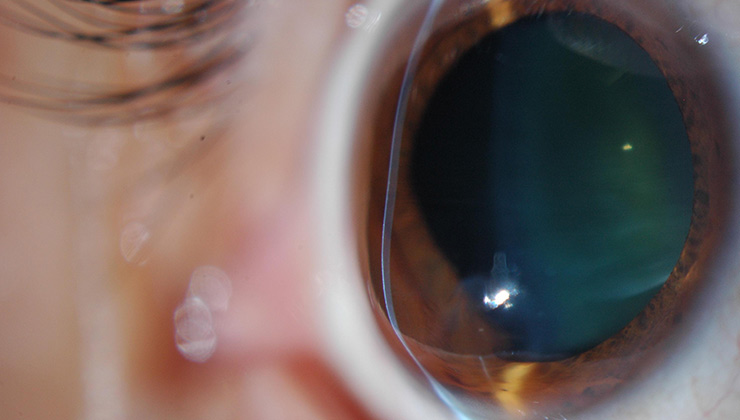

La microscopía especular nos permite realizar el estudio del endotelio corneal. Puesto que la distribución celular es prácticamente uniforme, mediante la microscopía se puede conocer el número, la forma y el tamaño de la población endotelial.

La microscopía especular nos da una imagen refleja de la interfase óptica que hay entre el endotelio corneal y el humor acuoso, aunque también puede usarse para obtener imágenes del epitelio y del estroma corneal, así como del cristalino.

El endotelio normal de una persona joven muestra, en la microscopía especular, un patrón regular de células hexagonales, la mayoría de ellas con el mismo diámetro, que pueden variar con la edad, los traumas, las patologías o los procedimientos quirúrgicos.

Para realizarla, no se precisa contacto. El centrado del ojo se realiza con luz de fijación y es recomendable que el paciente parpadee varias veces antes de la toma de la imagen para humedecer la superficie ocular y mejorar su brillo. Es obligatorio realizar la microscopía especular como una ayuda diagnóstica no invasiva para conocer el estado y la reserva fisiológica de la capa celular endotelial, debido a que una córnea transparente no es garantía de un endotelio corneal normal. Así pues, la realizamos de forma sistemática a nuestros pacientes antes de la cirugía de la catarata y de la cirugía del implante de lentes fáquicas.